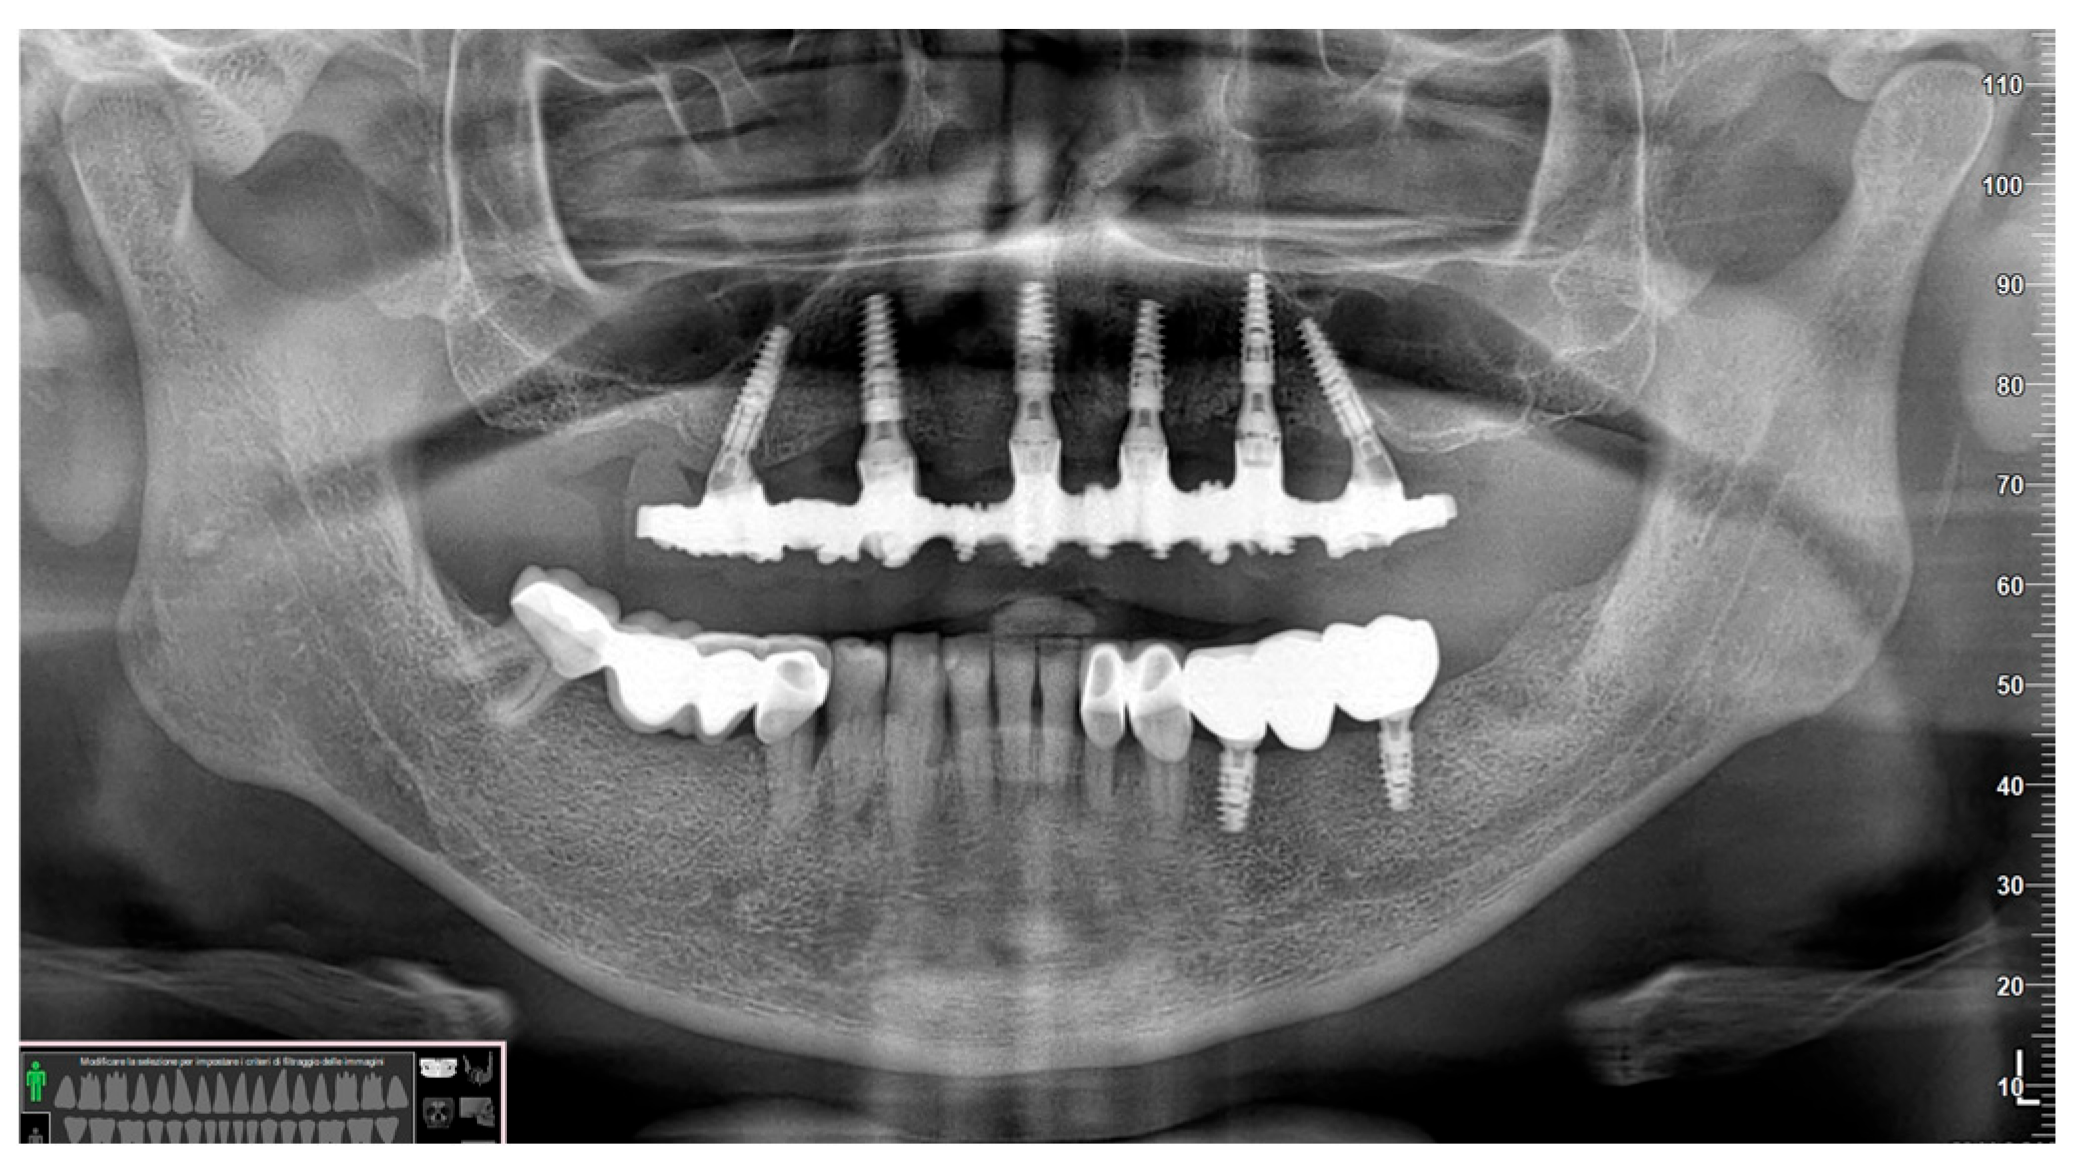

3. Results